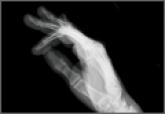

Bronchogenic Squamous Cell Carcinoma With Soft-Tissue Metastasis to the Hand: An Unusual Case Presentation and Review of the Literature

Carcinoma of the lung is the most common lethal form of cancer in both men and women worldwide. Orthopedic manifestations of lung cancer...